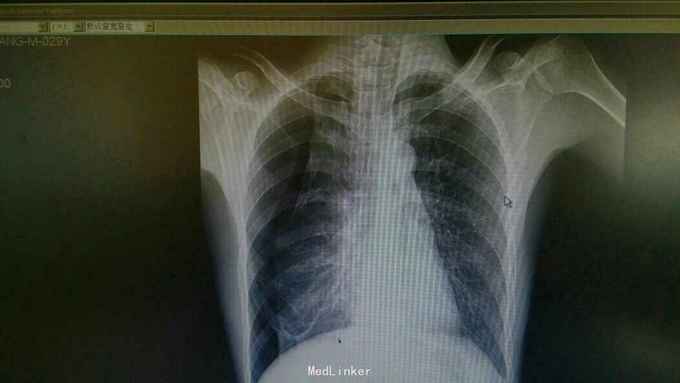

主诉:咳嗽,呼吸困难5天。 病史:患者5天前无明显诱因出现右侧胸痛,伴有咳嗽,呼吸困难,走路时呼吸困难加重,休息时可缓解,余无不适。 既往有肺结核病史。

查体:双侧呼吸运动不对称,右侧触觉语颤减轻,右肺叩诊过清音,右侧呼吸音减弱,余无特殊。 辅查:胸片可见右侧肺压缩60%,可见少量液体。考虑右侧液气胸。